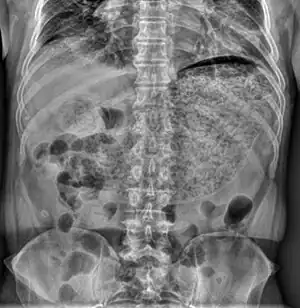

| X-ray showing a large amount of food in the stomach due to severe gastroparesis[1] | |

Gastroparesis can be diagnosed with tests such as barium swallow X-rays, manometry, and gastric emptying scans.[30] For the X-ray, the patient drinks a liquid containing barium after fasting which will show up in the X-ray and the physician is able to see if there is still food in the stomach as well. This can be an easy way to identify whether the patient has delayed emptying of the stomach.[31] The clinical definition for gastroparesis is based solely on the emptying time of the stomach (and not on other symptoms), and severity of symptoms does not necessarily correlate with the severity of gastroparesis. Therefore, some patients may have marked gastroparesis with few, if any, serious complications.

In other cases or if the X-ray is inconclusive, the physician may have the patient eat a meal of toast, water, and eggs containing a radioactive isotope so they can watch as it is digested and see how slowly the digestive tract is moving. This can be helpful for diagnosing patients who are able to digest liquids but not solid foods.[31]